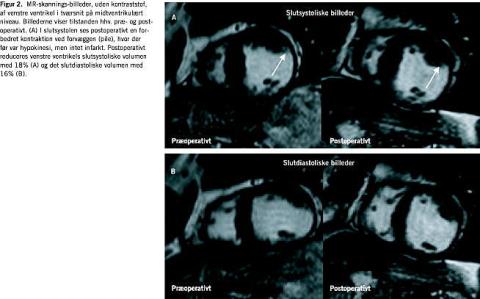

En 72-årig mand med stabil angina pectoris gennem 14 år, blev indlagt i 2001 på grund af pludselig indsættende retrosternale smerter med udstråling til begge arme. Ekg taget akut viste ST-elevation forenelig med inferiort myokardieinfarkt og patienten blev trombolyseret. Ved invasiv udredning med koronararteriografien blev der konstateret trekarssygdom, og patienten blev henvist til aortokoronar bypassoperation. MR-skanning med kontraststof udførtes dagen inden operationen og viste kontrastopladning svarende til, at der var transmural infarktudbredelse apikalt i bagvæggen og lateralvæggen af venstre ventrikel, mens infarktudbredelsen mere basalt i ventriklen var subendokardial (Fig. 1). MR-skannings-funktionsbillederne af venstre ventrikel viste en svært nedsat systolisk funktion. Venstre ventrikels slutdiastolisk volumen udmåltes således til 183 ml og et slutsystolisk volumen på 117 ml, (normalværdien for slutdiastolisk volumen er 115 ml og 36 ml for slutsystolisk volumen) [5], hvilket resulterede i en nedsat global ejektionsfraktion (EF) på 36%. Ved operationen anastomoseredes arteria mammaria til ramus interventricularis anterior a. coronariae sinistrae, der forsyner de forreste to tredjedele af septum interventriculare samt forvæggen af venstre ventrikel. En venegraft anastomeredes til arteria coronaria dextra som forsyner højre ventrikel samt den posteriore tredjedel af septum interventrik ulare og venstre ventrikels bagvæg. En anden venegraft anastomeredes til en margo obtusus gren fra ramus circumflexus, der forsyner lateralvæggen af venstre ventrikel. MR-skanningen med gadoliniumkontraststof fire måneder efter revaskulariserende behandling viste som ventet uændret infarktudbredelse (Fig. 1). Funktionsbillederne af venstre ventrikel viste nu et reduceret slutdiastolisk volumen på 153 ml, og et reduceret slutsystolisk volumen på 96 ml med en global EF på 38%. Regionalt sås en bedret kontraktion ved forvæggen, hvor der ikke var infarkt, samt ved basis af lateralvæggen, hvor infarktudbredelsen er subendokardial. Derimod var kontraktionen ophævet i det transmurale infarktområde apikalt i bagvæggen af venstre ventrikel både før og efter revaskulariserende behandling (Figur 2 A og B ).